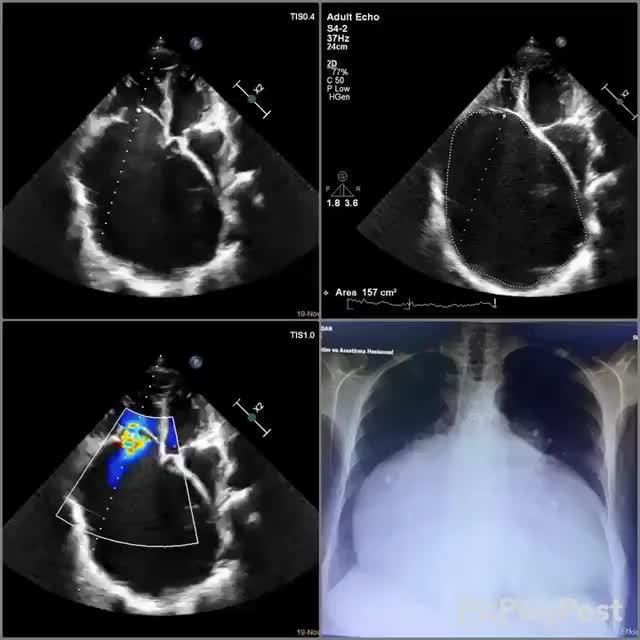

右心室肥大,太可怕了,单单高血压恐怕难以达到这样的程度